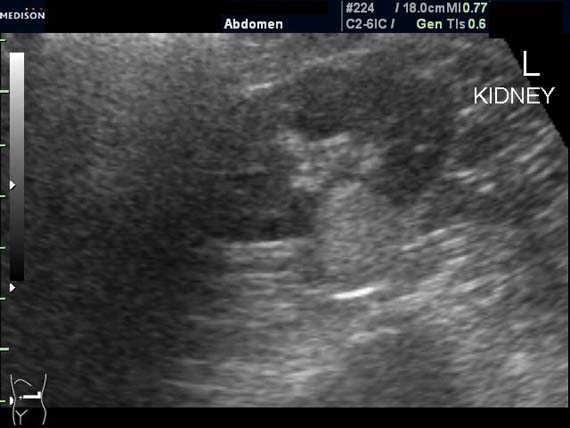

Женщина 50 лет. Жалоб нет. Обследование перед поездкой в санаторий по поводу дисфункции гепатобилиарной системы.

Случайная находка в нижней трети левой почки (не в полюсе, а по задне-медиальной поверхности).

Образование в левой почке

ПО УЗ-семиотике образование соответствует ангиомиолипоме (AML). По правилам в таких случаях необходимо выполнить КТ, доказать преимущественно жировой состав опухоли, затем проводить УЗ-наблюдение.

Согласен. Именно с таким диагнозом (ангиомиолипома) отправил на КТ. Особенностью случая ИМХО является заметный "выход" образования за контур почки (на 2/3 объема).

При ультрасонографии ангиомиолипома выглядит как округлое образование без капсулы с однородной внутренней эхоструктурой и четкими контурами; эхогенность ее чаще всего равна или чуть выше эхогенности перинефральной клетчатки [7]. Значительно реже эхогенность ангиомиолипом может быть равна эхогенности почечной паренхимы; такие опухоли состоят почти полностью из гладкомышечной ткани [8]. Иногда позади ангиомиолипомы может определяться слабая акустическая тень.